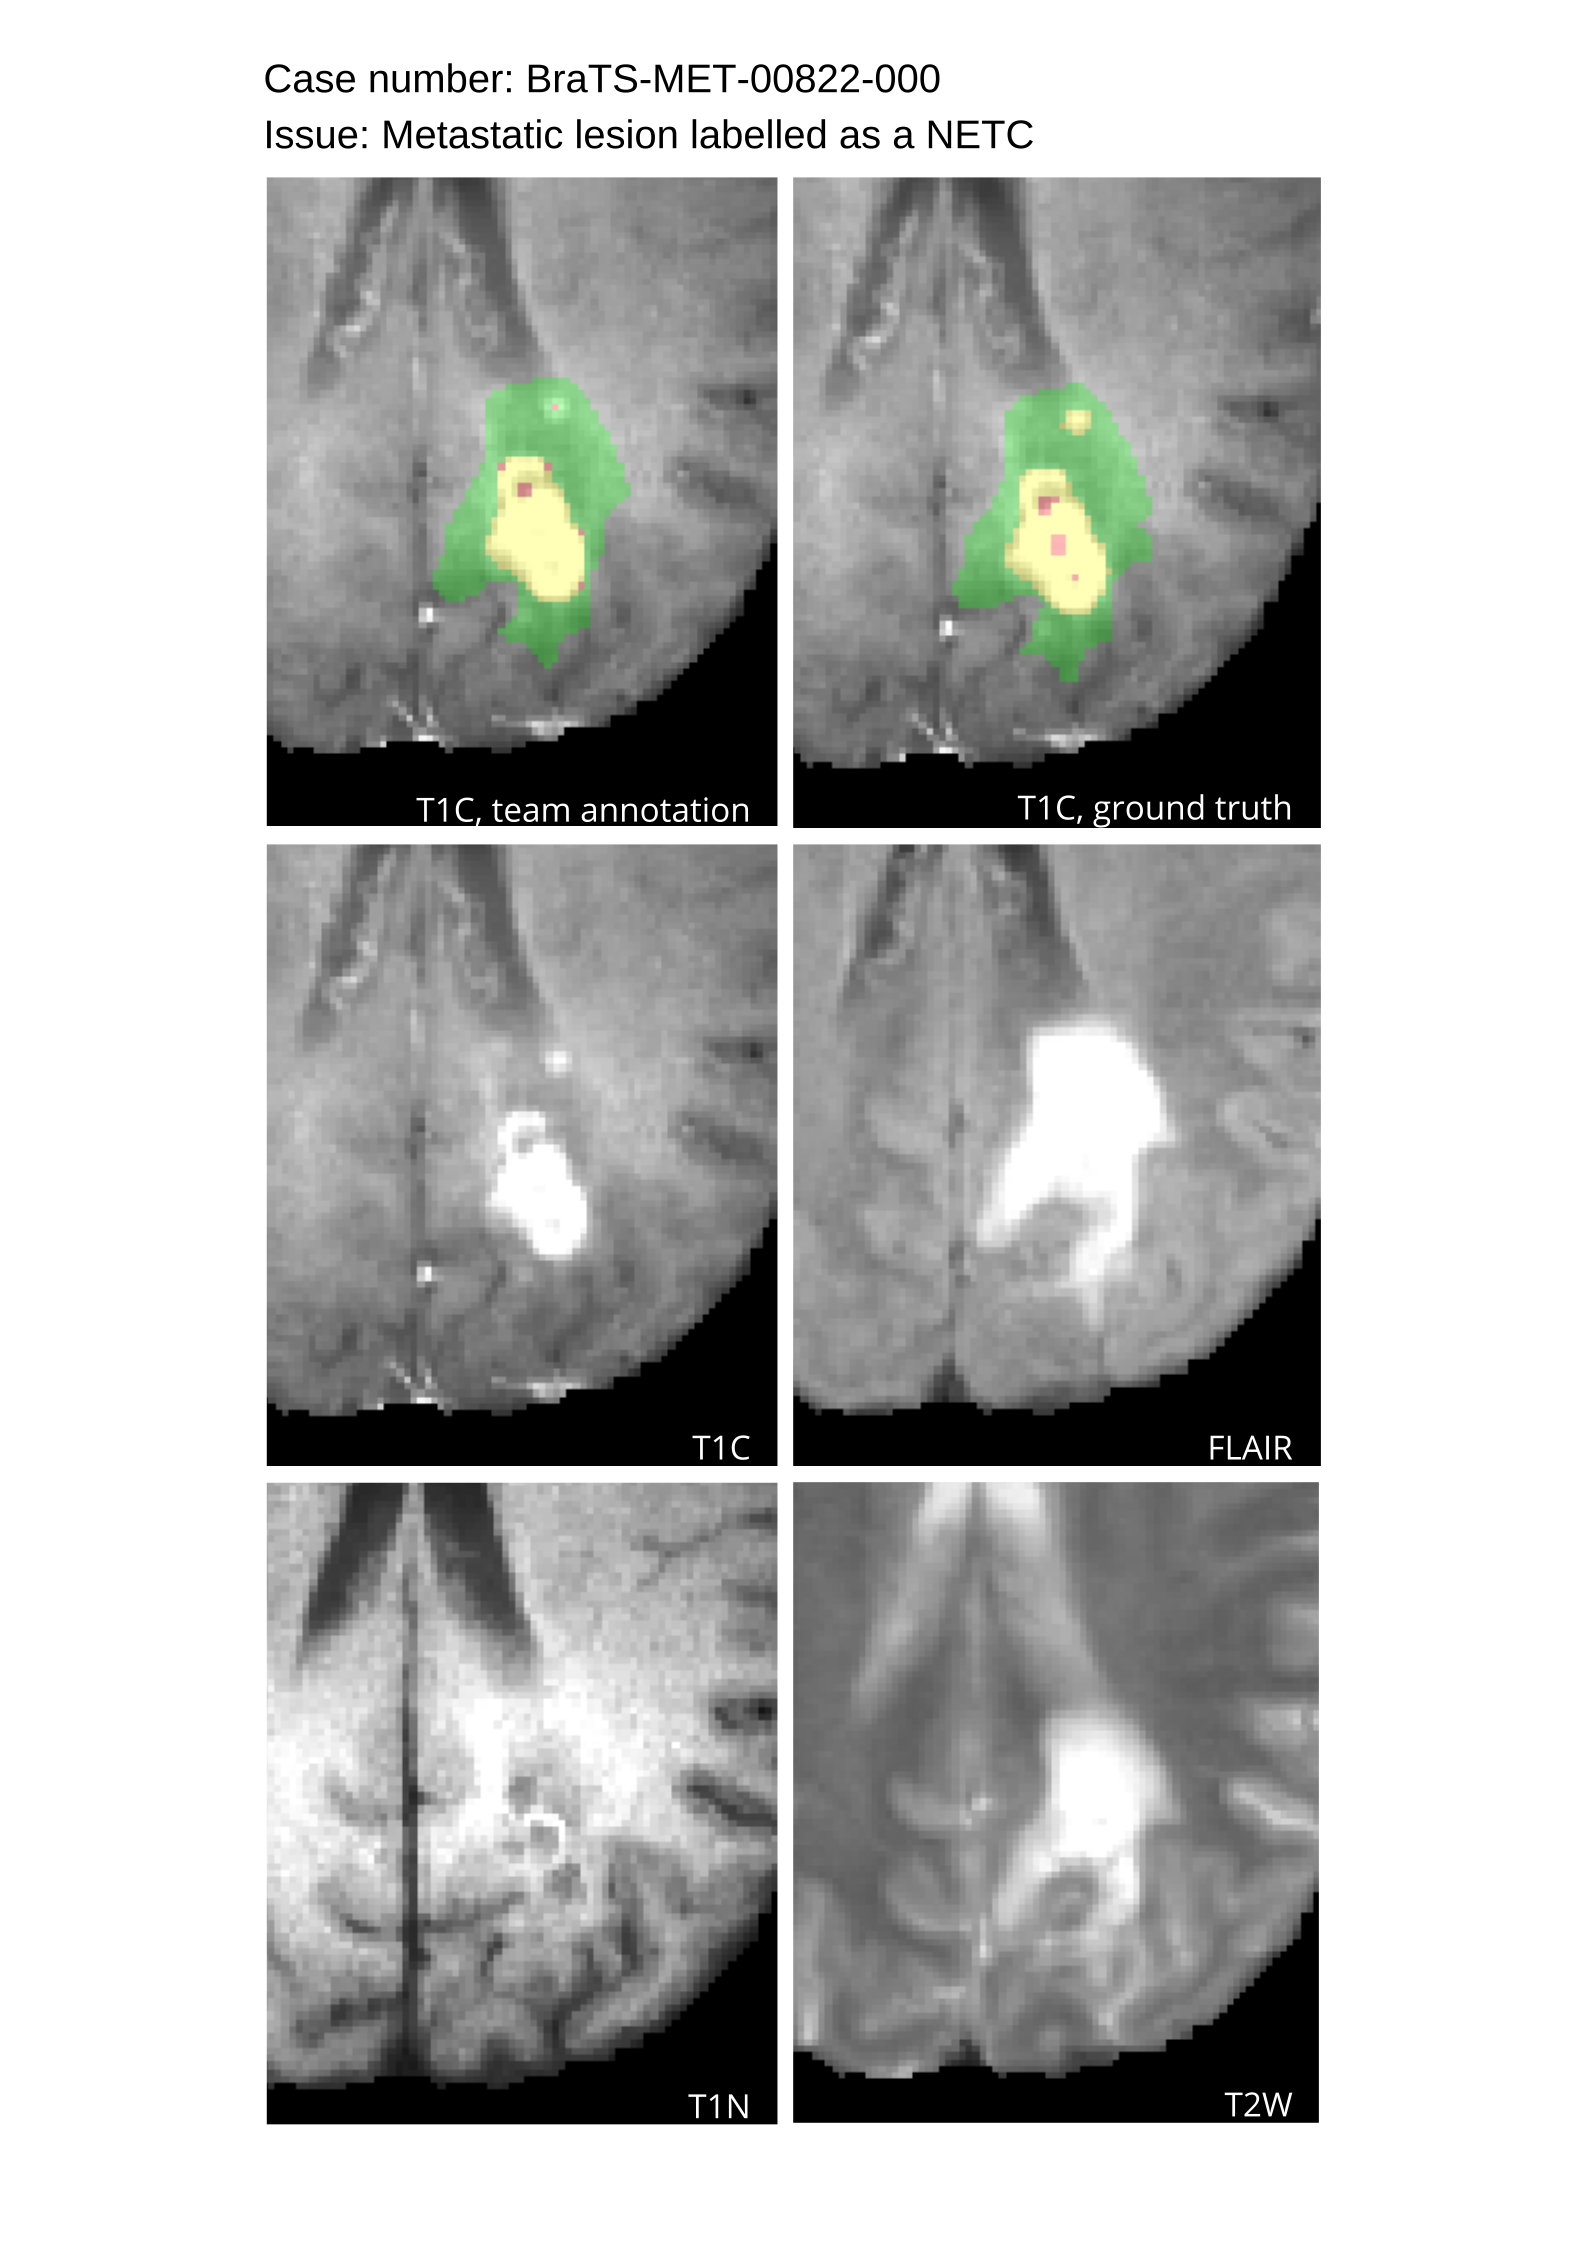

Table 4 provides the relative ranking for each team. Team NVAUTO ranked first in the challenge, with an average rank across subjects of 7.9 and a PatientWise mean of 0.38. Team SY placed second with a PatientWise mean of 0.41 across all patients. The supplementary material depicts the pitfall cases with figures illustrating the false positives or missed lesions.